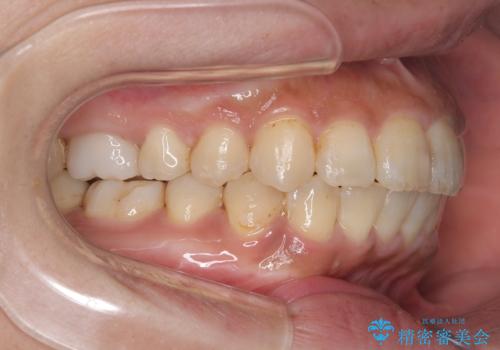

ワイヤー矯正(審美装置)非抜歯 治療期間:1年8か月

一日に物を口にする回数が多い方はマウスピース矯正における推奨装着時間を守ることや、その都度歯磨きをすることが難しいため、ワイヤー矯正での治療となりました。

途中、大臼歯の遠心移動のためリンガルアーチを使用しています。